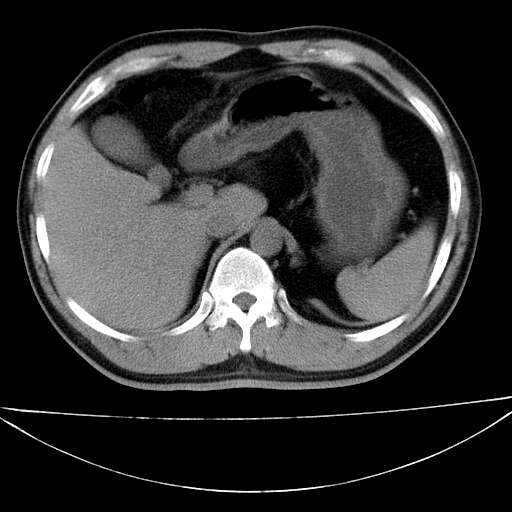

标题: CT21921:腹膜后腔肿物。患者男39Y。体检。增强扫描时间欠准 [打印本页]

标题: CT21921:腹膜后腔肿物。患者男39Y。体检。增强扫描时间欠准

左侧膈肌脚外缘见一结节样软组织影,密度较均匀,与胸膜关系稍密切,增强轻度强化;考虑来自胸膜良性病变(胸膜纤维瘤可能)。建议加扫胸部ct检查。

2、左下膈肌脚外缘结节状病变,与胸膜交界面呈锐角,胸膜下脂肪线可见,定位于肺内,考虑支气管囊肿或肺隔离征可能性大。

1)考虑左肺下叶后基底段(或左下胸后壁胸膜)软组织团块,性质待定;建议行进一步检查。2)左肾结石。

左膈肌连续性中断,左侧膈疝可能性大.

左膈肌角后腹膜腔见肿物影,其内见脂肪密度灶及软组织密度灶,强化不明显。病灶大部在后腹膜内。考虑异位嗜铬细胞瘤或脂肪肉瘤、畸胎瘤

考虑左肺下叶后基底段肺隔离症?胸膜间皮瘤?

左下肺隔离症,可见从胸主动脉发出异常血管供应